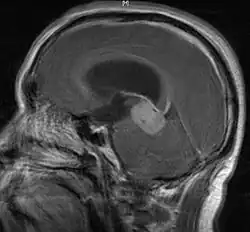

• Mainly located in midline structures, suprasellar region or pineal gland, also basal ganglia and hypothalamus

• Natural spread believed to be along subependymal lining of 3rd and 4th ventricles, leading to intraventricular relapse before spinal dissemination

Location

• Whole ventricular volume: 3rd, 4th, lateral, prepontine cistern

• Involved field volume: pre-chemotherapy volume + clinical margin 1-1.5 cm